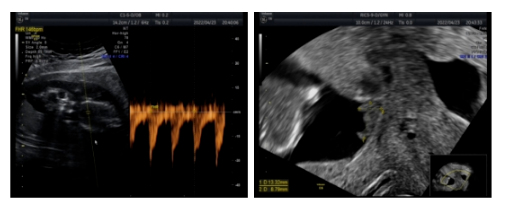

腹腔镜下子宫肌瘤剔除术(单孔)+卵巢扭转松解术

超声(2022-04-23):宫内孕活胎,羊水最大平面32mm,宫颈管闭合段长度34.2mm;盆腔后陷凹内液性暗区深约23mm。